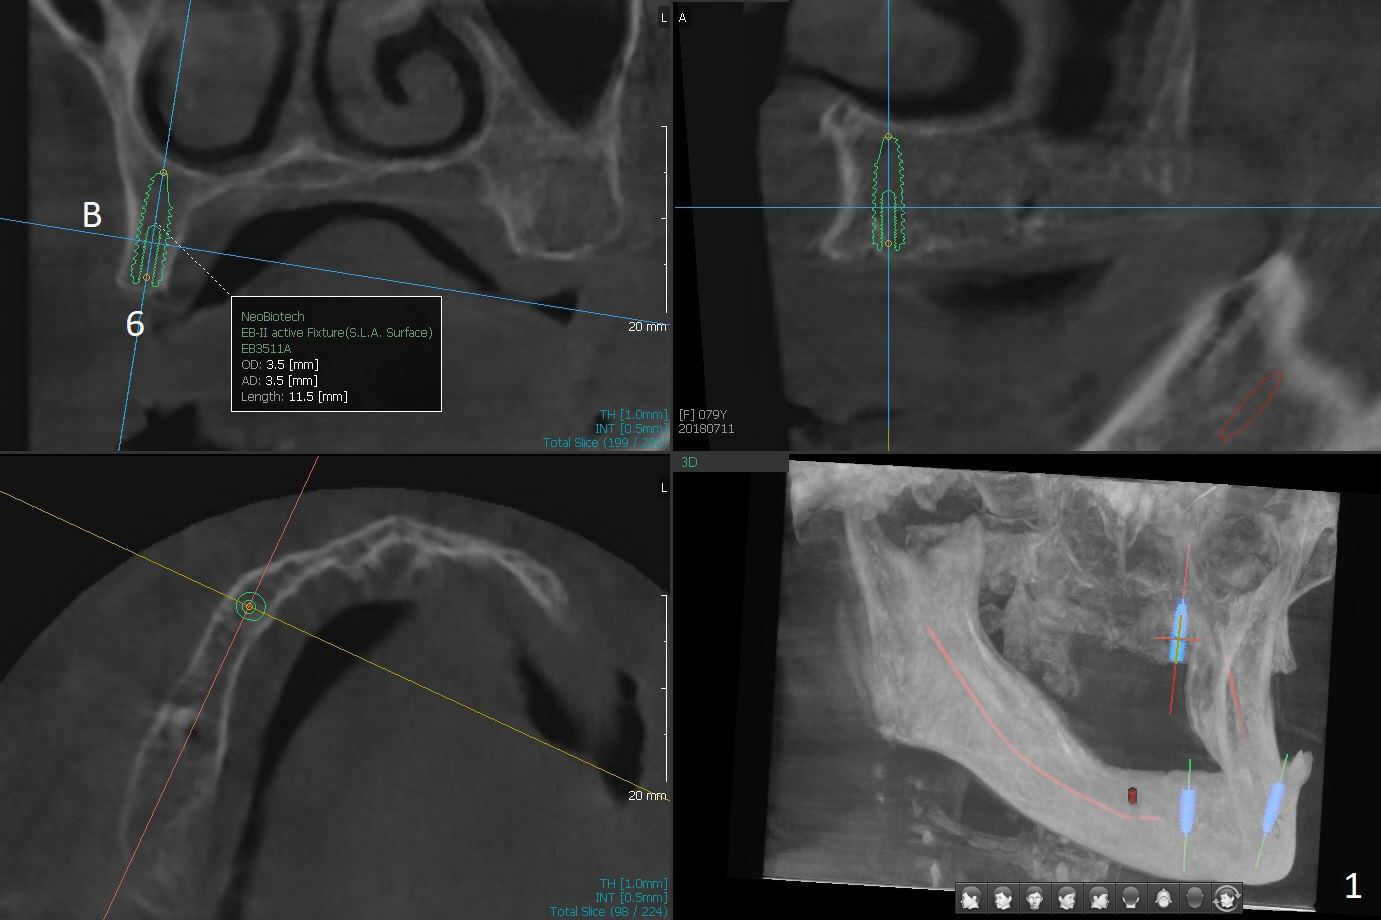

A 80-year-old woman wants to correct cross bite of complete dentures (Class II relationship). It seems that implant supported overdentures can make it possible (retention). Six implants will be placed in the maxillary canine and 2nd premolar and 2nd molar areas with surgical guide (Fig.1-6 (anterior ridge narrow)). Bone density is low. Prepare soft reline.